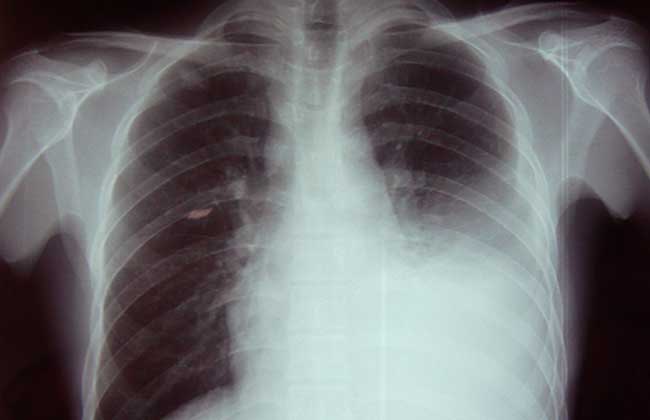

大多数结核性胸膜炎是急性病,症状主要表现为结核的全身中毒症状和胸腔积液所致的局部症状。结核中毒症状主要表现为发热、畏寒、出汗、乏力、食欲不振、盗汗。局部症状有胸痛、干咳和呼吸困难。胸痛多位于胸廓呼吸运动幅度最大的腋前线或腋后线下方,呈锐痛,随深呼吸或咳嗽而加重。由于胸腔内积液逐渐增多,几天后胸痛逐渐减轻或消失。积液对胸膜的刺激可引起反射性干咳,体位转动时更为明显。积液量少时仅有胸闷、气促,大量积液压迫肺、心和纵隔,则可发生呼吸困难。积液产生和聚集越快、越多,呼吸困难越明显,甚至可有端坐呼吸和发绀。